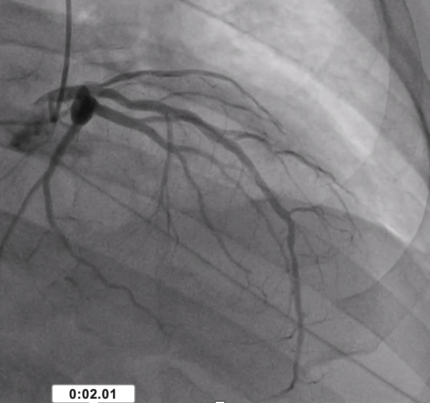

A 66-year-old male with a history of non-obstructive coronary artery disease [Image 1], unprovoked pulmonary embolism, hypertension, and diastolic heart failure presented with left-sided chest pressure three weeks post-NSTEMI. High-sensitivity troponin was elevated at 141 ng/L. He concurrently reported fingertip pain, intermittent confusion, and dizziness.